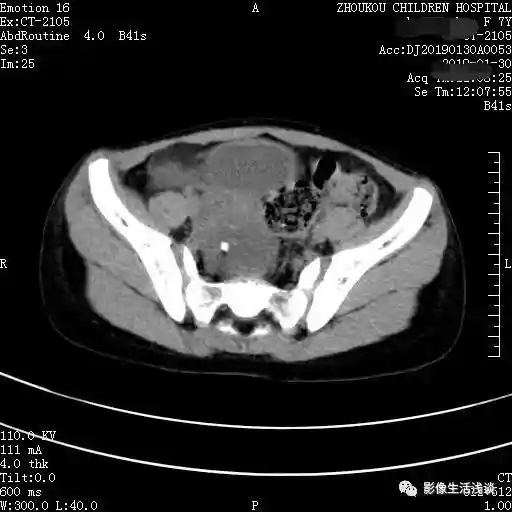

今天给大家分享的第一病例7岁女孩,以右下腹痛来诊,在CT平扫检查中我们发现:右侧附件区可见囊性占位,以液性为主,其内可见脂肪成分及点状钙化影,边界清晰。考虑:右附件区畸胎瘤